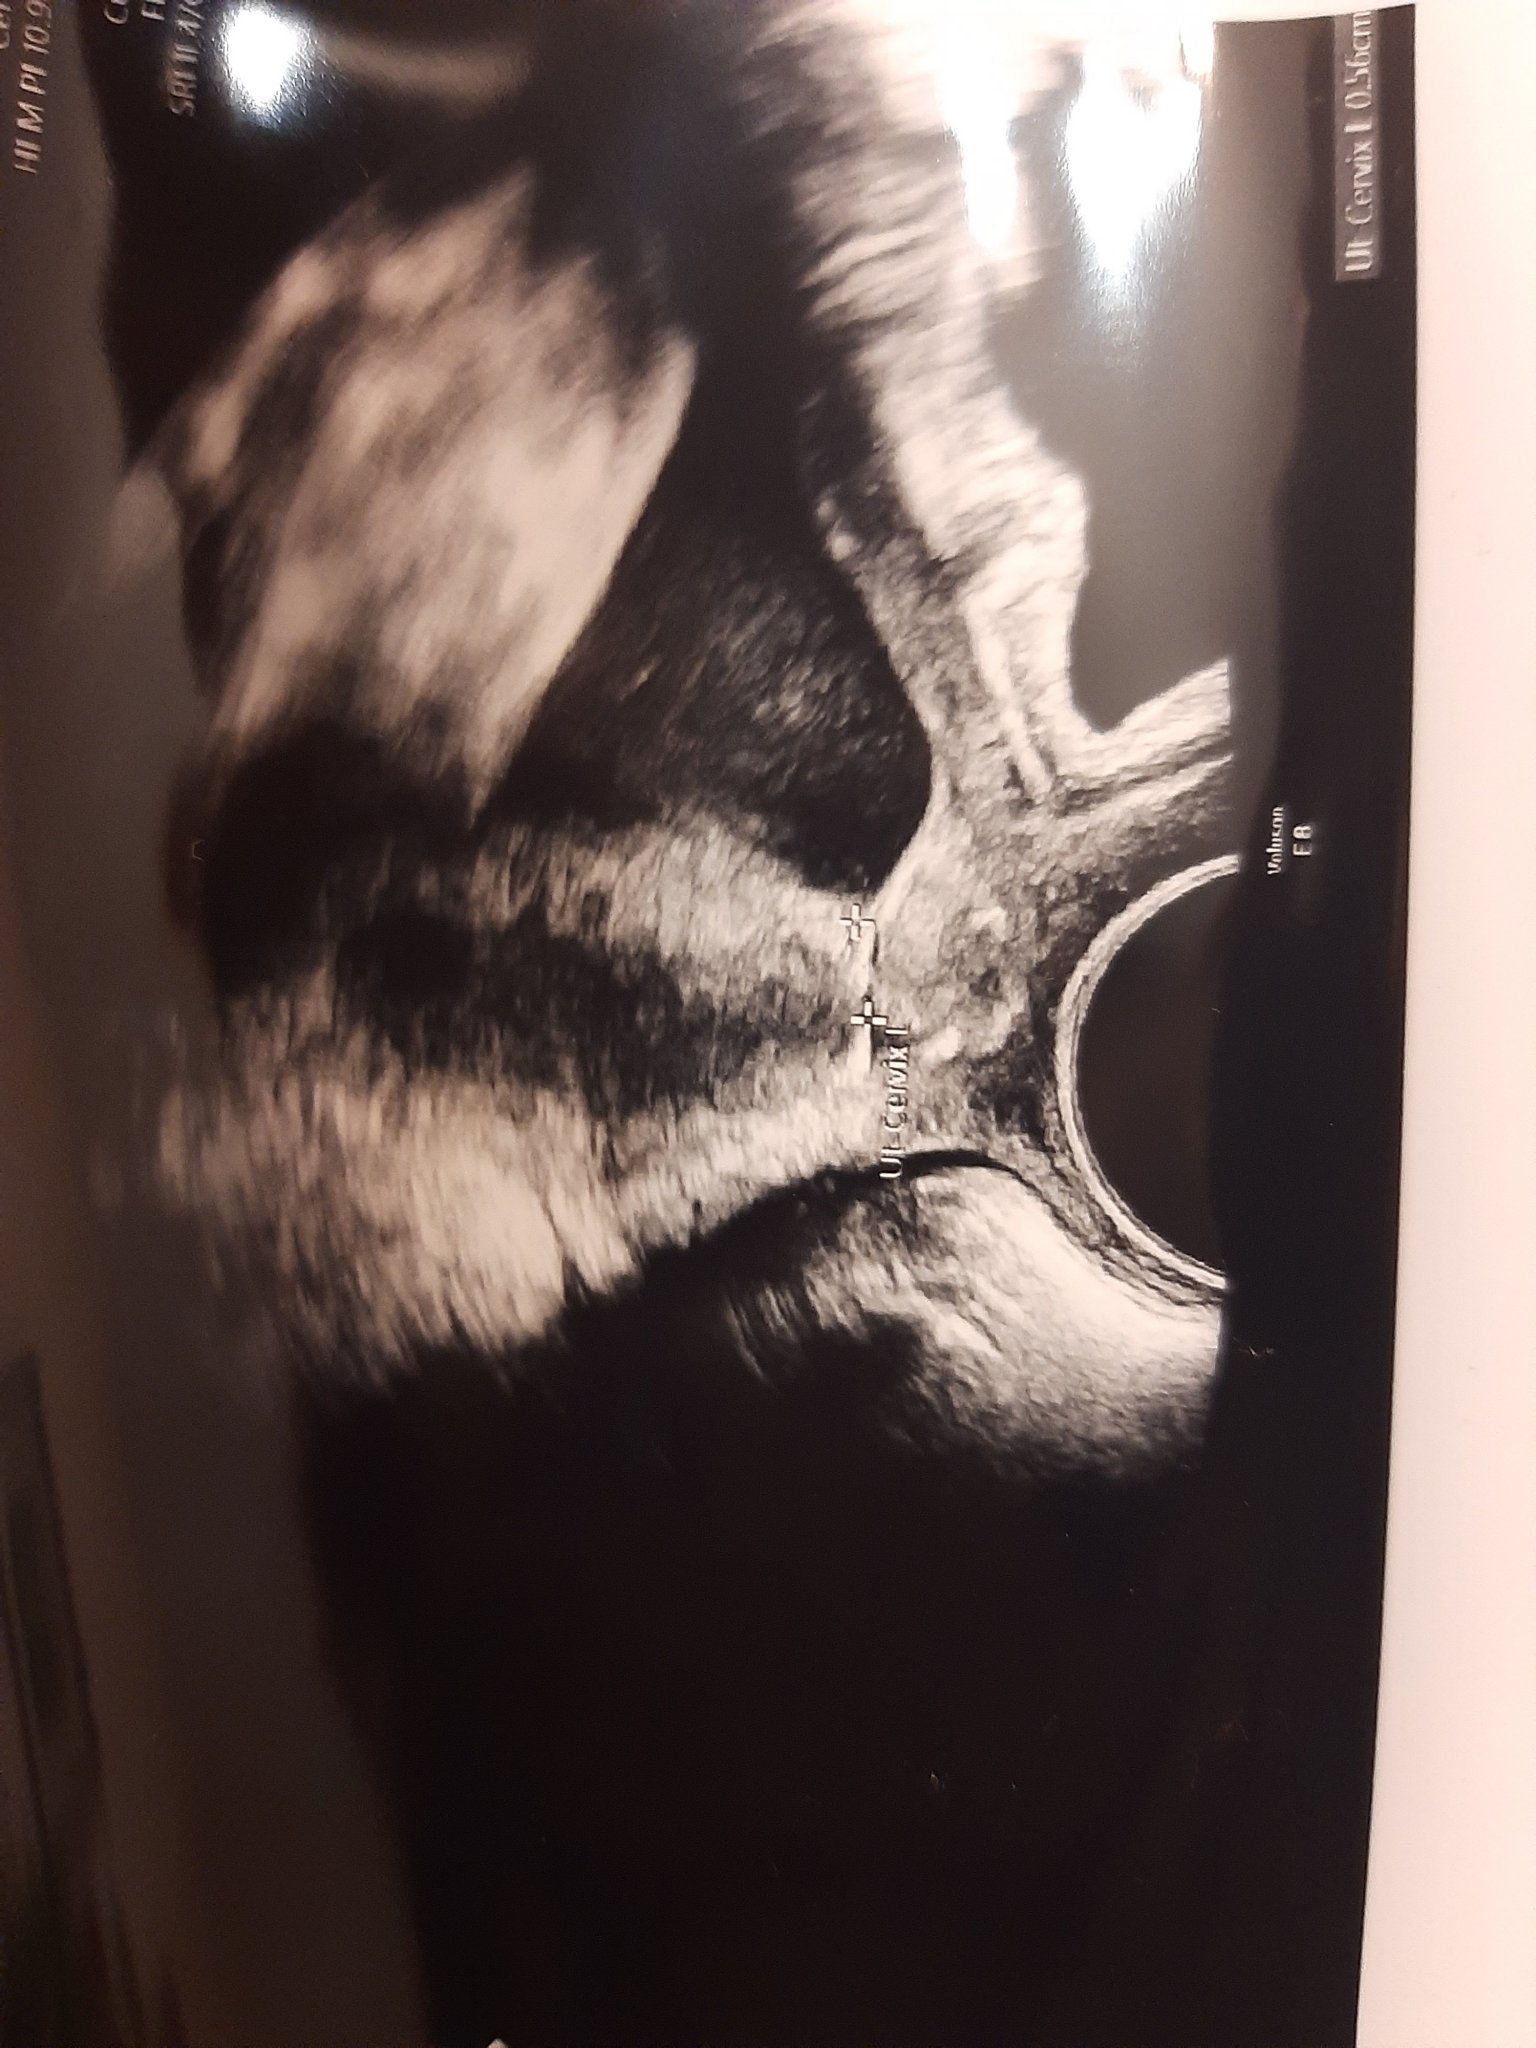

Загледах се в снимката на шийката и ми се струва, че не е измерена както трябва, моля някоя мама от вас ако разбира нека изкаже мнение

Измерването след конизация и серклаж е трудно дори за АГ. Ако имаш съмнения помоли за втора консултация, но нека да е от лекар-специалист, а не от приятелка, съфорумка и т.н. Понякога близките на пациентите в стремежа си да помогнат създават много стрес, а сега е важно да си спокойна и да имаш доверие на екипа, който те обгрижва Hug